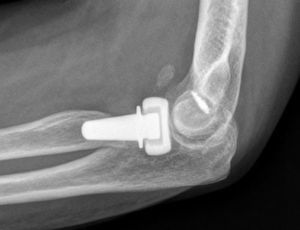

In all cases, the prosthetic substitution of fracture fragments of the radial head was performed with a unipolar prosthesis: Ascension® Modular Radial Head (MRH) (Ascension Orthopedics, Austin, TX, USA), which comprised of 2 modular components, a stem and a head. The prosthesis has been anatomically designed to articulate with the ulna in a pronosupination movement and also to allow elbow flexion–extension through its articulation with the humeral capitellum.

The implant head was coated with a pyrolytic carbon layer deposited on a high-strength graphite substrate. It also contained an ultra-high molecular weight polyethylene (UHMPE) insert. The stem was made of titanium with a pyramidal design, so as to prevent rotation. Introduction of the stem into the canal molded in the radial neck was performed using a pressure anchor, without the use of cement.

Three of the 9 patients (33%) who presented complications required a new surgical intervention for the treatment of their lesions. In one case, the patient suffered a dislocation of the prosthesis in the immediate postoperative period, which was treated by replacing the implant with another of a smaller size. The other 2 cases corresponded to painful aseptic loosening, with radiolucency around the entire prosthetic stem, requiring revision surgery. One was a patient who had suffered a “terrible triad” and who developed pain symptoms in the radial side of the elbow, with periprosthetic osteolysis, heterotopic ossifications and severe ulnohumeral osteoarthritis (or arthrosis) 4 years after the surgery (Fig. 3A and B). The patient was reintervened, with radial implant resection arthroplasty which led to the cessation of pain symptoms and a good functional result (Fig. 4A and B). The initial lesion in the other patient was an Essex-Lopresti fracture-dislocation which began with pain in the radial head, associated with signs of radiolucency around the prosthetic stem, 3 years after the initial surgery. The reoperation consisted of replacement with a new cemented prosthesis, leading to cessation of symptoms in the early postoperative period.

The action of inserting the prosthesis through a pressure anchor required a very close approximation to the native anatomy, so that the new implant could function properly in the different positions of the elbow and forearm. This attachment of the stem to the medullary canal conferred greater stability to the assemblage, with radio-capitellar dislocation being infrequent.32 Cementing of the prostheses was usually reserved for revision surgery or tumoral cases, so its use for posttraumatic conditions was rare.31